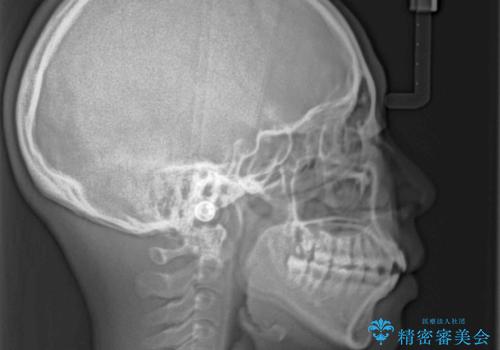

舌の突出癖により上下前歯は接触できず、更には前方に押し出されて出っ歯になっている状態でした。

上下左右の第一小臼歯4本を抜歯し、ワイヤー装置での抜歯矯正を行っていくのですが、原因である舌の突出癖を改善しないことには治療がうまく進められないため、舌のトレーニングを徹底するよう指導していくこととしました。